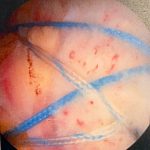

Surgical pictures

Finished repair

You can see from the bone spur outlined in red above that my tear was an caused by repetitive micro trauma over time. Eventually, the tendon became tattered and torn. All the years of weight training probably contributed to some of this, as well as my type 2 acromion. I ended up with three total anchors and a suture bridge repair.